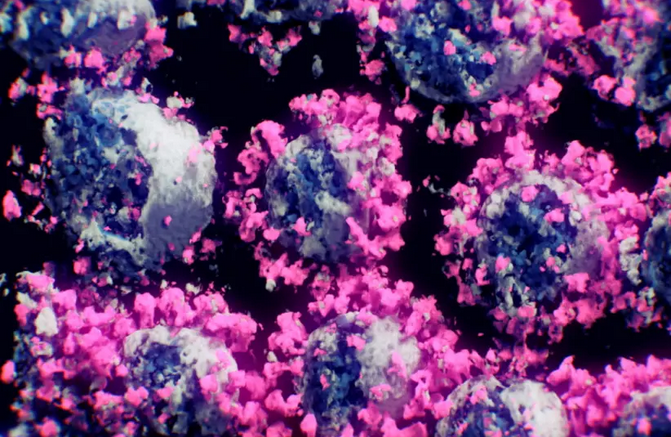

Η καινοτόμος θεραπεία κατά του covid 19 βάζει φραγμό στο σημείο εισόδου του ιού στο κύτταρο

Το

νέο φάρμακο εμποδίζει το σημείο εισόδου του κορωνοϊού στο κύτταρο χωρίς

να βλάψει την ενζυματική λειτουργία του σημείου εισόδου.

Μια

καινοτόμος θεραπεία για τον COVID-19 χρησιμοποιεί ένα μοριακό «σούπερ

φελλό» για να μπλοκάρει το σημείο εισόδου που χρησιμοποιείται από τον ιό

SARS-CoV-2 για να εισέλθει στο κύτταρο, παρακάμπτοντας ζητήματα που θα

μπορούσαν να προκύψουν με άλλες θεραπείες που στοχεύουν σε ακίδα

πρωτεΐνης στον ιό, ανέφερε το Ινστιτούτο Επιστήμης Weizmann.

Η διαδικασία σάρωσης παρείχε επίσης ισχυρά στοιχεία υπέρ της υπόθεσης

ότι ο νέος κορωναϊός γίνεται πιο μεταδοτικός καθώς μεταλλάσσεται για να

έχει καλύτερη προσαρμογή στην ACE2.

Μετά τον πρώτο γύρο επιλογής, οι

εργαστηριακές παραλλαγές με πιο δεμένες δυνατότητες σύνδεσης με το

ένζυμο μιμήθηκαν τις μεταλλάξεις που υπάρχουν στις περιοχές δέσμευσης

των πιο μεταδοτικών στελεχών SARS-CoV-2.

Η παραλλαγή Delta,

ωστόσο, βασίζεται σε ένα διαφορετικό τρόπο για να είναι πιο μολυσματική

αποφεύγοντας εν μέρει την ανίχνευση από το ανοσοποιητικό σύστημα.